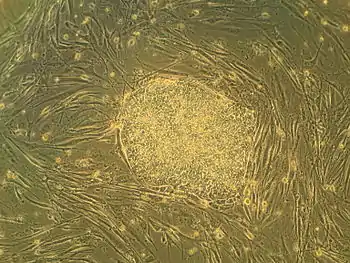

A descoberta da insulina na Universidade de Toronto em 1921 é considerada um dos eventos mais significantes da história da medicina.[121][122] A existência das células-tronco foi descoberta na universidade em 1963, formando a base para o transplante de medula óssea, e todas as pesquisas subsequentes sobre célula-tronco adultas e embriônicas.[123] Esta foi uma das primeiras descobertas sobre células-tronco na universidade, que inclui a identificação das células-tronco do pâncreas e da retina.[124][125] A célula-tronco cancerígena foi identificada em 1997 por pesquisadores da universidade,[126] que posteriormente associaram células-tronco com leucemia, tumores cerebrais e câncer colorretal.[127][128]